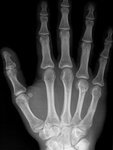

MC-4 Kopffraktur

ich habe mir leider vor ca. 4 Wochen die rechte Hand gebrochen, ich denke der Gips wird wohl nächste Woche runterkommen. Was meint ihr wie lange es dauert, bis ich die Hand wieder vollständig belasten kann ?

Ja das Handgelenk war mit fixiert. Es geht dabei um den Knochen vom Ringfinger, auf dem Handrücken. Schmerzen sind Nebensache, No Pain No Gain :D

Och das hält sich noch in Grenzen, hatte schon schlimmere Brüche, ist auch nur an der Stelle gespalten und leicht gestaucht :(

Sieht man kaum :D

• aua2.jpg